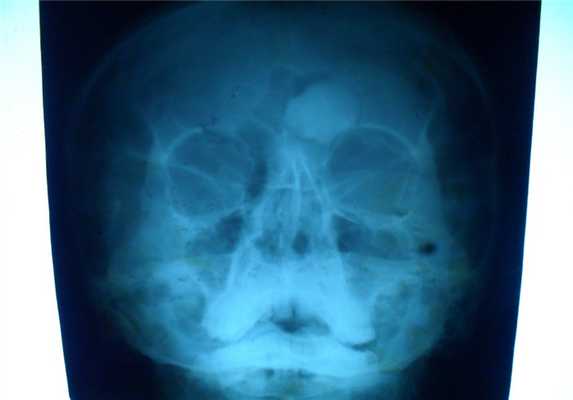

При локализации гемангиомы в плоских костях свода черепа происходит:

- вздутие кости и разрушение коркового слоя, надкостница приподнимается опухолью,

- характерен структурный рисунок - из центра опухоли к ее поверхности лучеобразно или веерообразно рассыпаются тонкие и более грубые костные балки.

Внутрикостная гемангиома черепа может сопровождаться головной болью, которая обуславливается постоянным раздражением мозговых оболочек. Иногда можно нащупать на черепе небольшую довольно плотную выпуклость - в этом случае безотлагательно посетите специалиста и пройдите назначенную диагностику. В АЦМД-Медокс успешно диагностируются гемангиомы любой локализации при помощи МРТ и СКТ.

Гемангиома в плоских костях черепа - не частое образование, которое располагается преимущественно в диплоическом слое. Имеется разряженное строение губчатого вещества и толстые костные трабекулы, радиально расходящиеся в стороны. Очаг разряжения губчатого вещества в толще диплоического слоя определяется как зона↓плотности на КТ (стрелка на рис.1221) и↑МР-сигнала на Т2 и Flair (головки стрелок на рис.1219-1221).